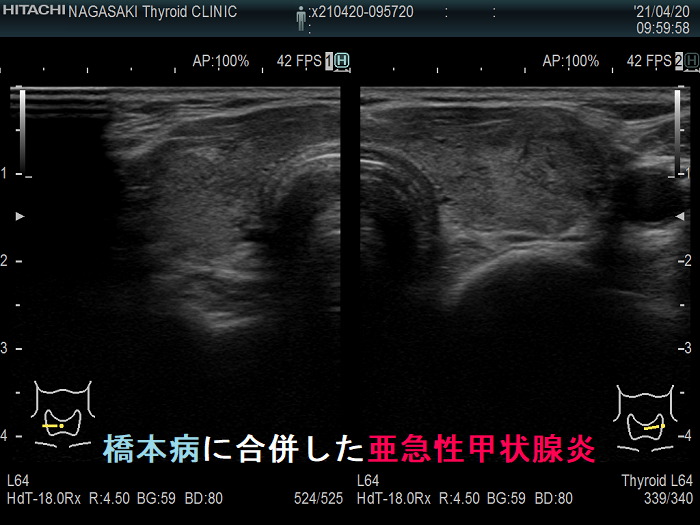

亜急性甲状腺炎

亜急性甲状腺炎は、甲状腺に痛みや不快感を引き起こす、まれなタイプの甲状腺炎です。この疾患を持つ人は甲状腺機能亢進症の症状も示し、その後甲状腺機能低下症の症状を発症します。亜急性甲状腺炎は一時的なことが多いですが、治療せずに放置すると永続的な合併症を引き起こす可能性があります。

他の形態の甲状腺炎とは異なり、亜急性甲状腺炎はウイルス感染に関連していると考えられています。ウイルスに反応して甲状腺が腫れ、ホルモン生成が阻害される可能性があります。これにより炎症が起こり、さまざまな症状が引き起こされます。